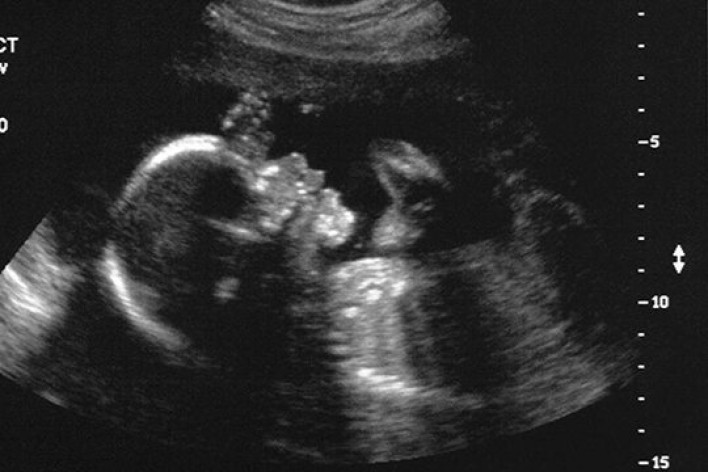

Աննախադեպ.3 ծնողների երեխա կծնվի

New Scientistամսագիրը հայտնում է,որ Մեծ Բրիտանիայի կարգավորող մարմինները հաստատել են 3 ծնողների երեխաների բեղմնավորման 2 փորձ: Մեթոդը մշակել է ղազախ-ամերիկացի կենսաբան Շուքրաթ Միթալիփովը: Փորձագետները սպասում են, որ 3 ծնողների առաջին երեխաները կարող են ծնվել Մեծ Բրիտանիայում արդեն 2018 թ.: Գիտնականները հանում են բեղմնավորված ձվաբջջի միջուկը և այն տեղափոխում են դոնորական ձվաբջջի մեջ, որի միջուկը նախապես հեռացվում է: Հետո այն փոխպատվաստում են իրական կամ փոխնակ մոր արգանդի մեջ: